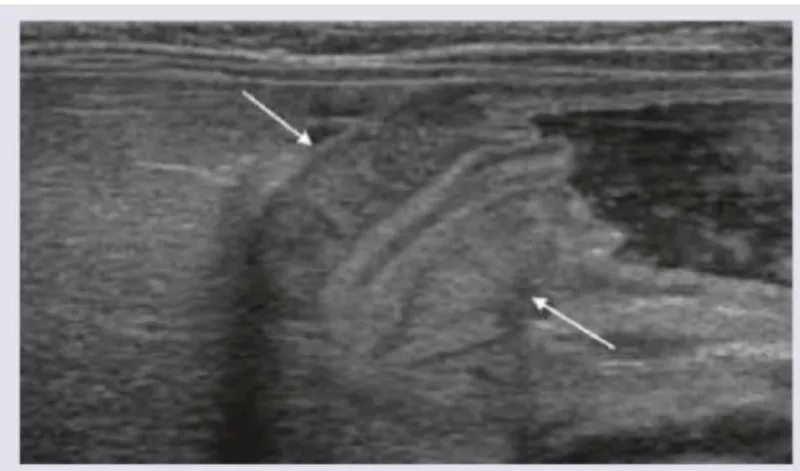

- First-line imaging: Ultrasound (children/women of childbearing age); CT if inconclusive

- Appendix diameter: >6mm on imaging suggests appendicitis

| Ovarian torsion | Sudden severe pain, vomiting, adnexal mass | Doppler USS: absent flow |